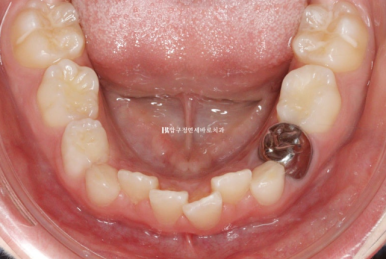

병원에 처음 온 날 모습입니다.

문제점을 나열해보자면

과개교합 (앞니가 깊게 물림)

덧니 (삐뚤빼뚤)

후속 영구치가 나올 공간 부족